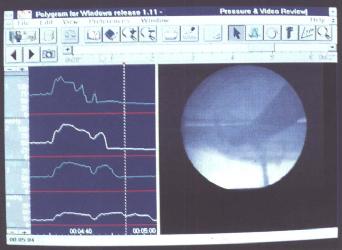

同步吞钡透视及测压检查(图2.5)

为评价吞咽异常可同步进行咽部测压及X线透视。钡透视显影与生理指标记录同步进行,检测同步显示,并以数字方式记录在同一计算机上。

图2.5同步钡透及测压检查(图取自Medtronic GastroIntestinal).

X线电视诊断